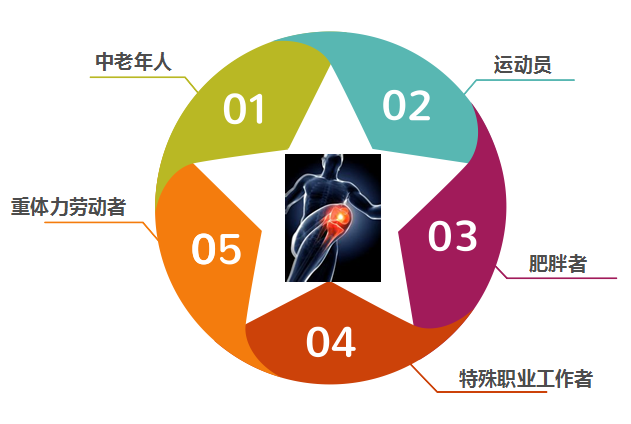

CARTISTEM适用人群

CARTISTEM适用于由退行性或反复外伤引起的ICRS IV级膝骨关节炎患者。CARTISTEM是目前50-70岁严重膝骨关节炎患者的首选,但不限于该年龄段,目前所有接受治疗的患者中:年龄最小者为12岁,年龄最大者94岁。

膝骨关节炎高发人群

(需长时间站立者、登山爱好者等)